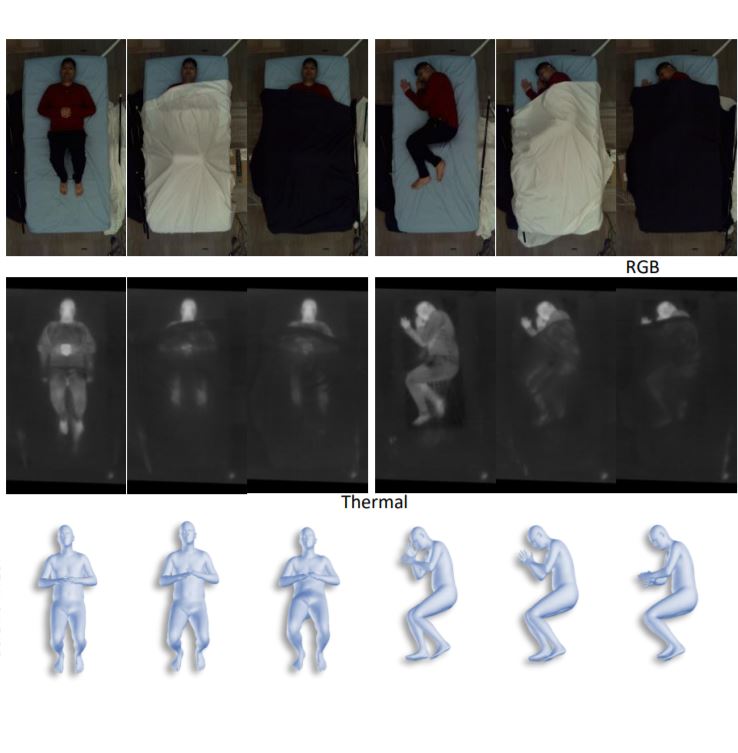

Automated Patient Positioning with Learned 3D Hand Gestures

We propose an automated patient positioning system that utilizes a camera to detect specific hand gestures from technicians, allowing users to indicate the target patient region to the system and initiate automated positioning. Our approach relies on a novel multi-stage pipeline to recognize and interpret the technicians’ gestures, translating them into precise motions of medical devices.

Self-supervised 3D Patient Modeling with Multi-modal Attentive Fusion

We propose a generic modularized 3D patient modeling method consists of (a) a multi-modal keypoint detection module with attentive fusion; and (b) a self-supervised 3D mesh regression module.

This paper considers the problem of 3D patient body modeling. Such a 3D model provides valuable information for improving patient care, streamlining clinical workflow, automated parameter optimization for medical devices etc. We present a novel robust dynamic fusion technique that facilitates flexible multi-modal inference, resulting in accurate 3D body modeling even when the input sensor modality is only a subset of the training modalities.

The COVID-19 pandemic, caused by the highly contagious SARS-CoV-2 virus, has overwhelmed healthcare systems worldwide, putting medical professionals at a high risk of getting infected themselves due to a global shortage of personal protective equipment. To help alleviate this problem, we design and develop a contactless patient positioning system that can enable scanning patients in a completely remote and contactless fashion. Our key design objective is to reduce the physical contact time with a patient as much as possible, which we achieve with our contactless workflow.